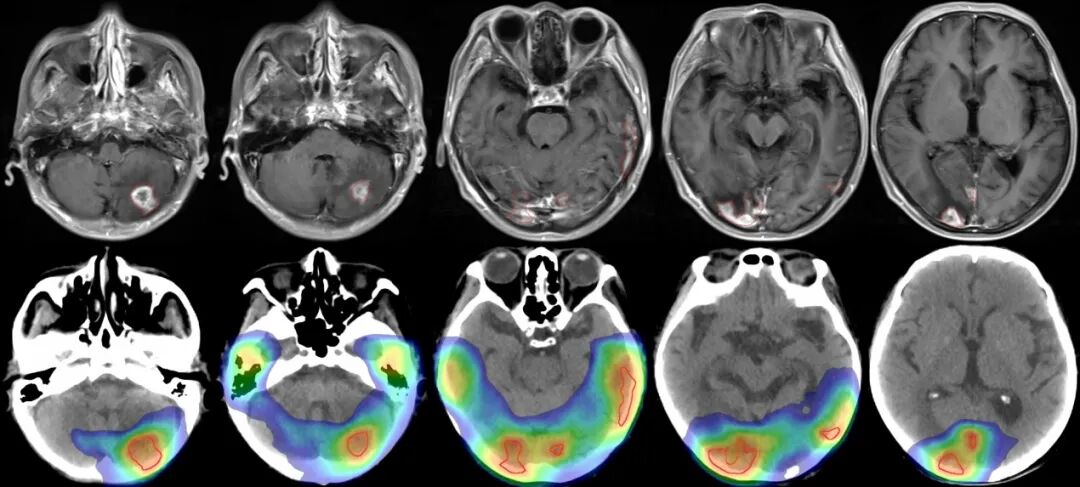

考慮到該患者年齡輕,中樞神經(jīng)系統(tǒng)外腫瘤病灶良好,應(yīng)給予相對(duì)積極的治療方案。根據(jù)患者病灶位置等情況,并充分利用速銳刀精準(zhǔn)聚焦照射的劑量?jī)?yōu)勢(shì),潘振宇教授團(tuán)隊(duì)為患者制定了積極的治療方案,力爭(zhēng)一次性將顱內(nèi)轉(zhuǎn)移瘤病灶徹底控制。

圖注:患者放療區(qū)域以及劑量分布圖